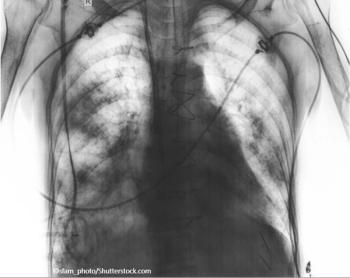

Beth is age 52, smokes 2 packs of cigarettes a day, gets breathless in cold weather, and has had "bronchitis" twice this year. What's your diagnosis?